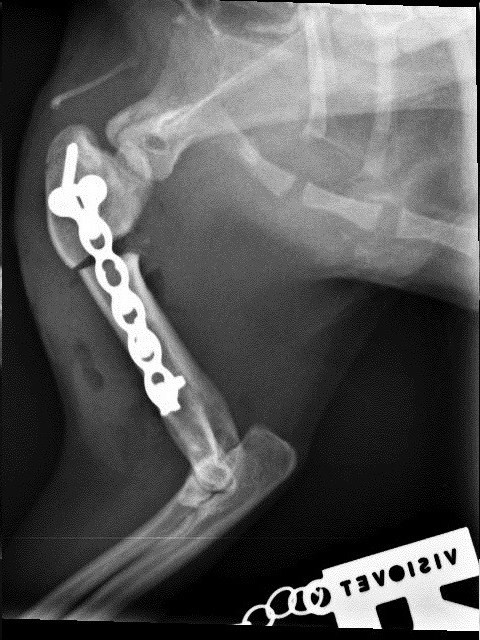

Die kleine verschmuste Maus ist so tapfer, inzwischen hat sie bereits beide OPs gut überstanden. Bei der ersten OP wurde die Biegung im Oberarm herausgeschnitten und der Oberarm in gestreckter Position mit einer Platte befestigt. Die Röntgenkontrolle hat gezeigt, dass der Knochen schon gut verheilt ist, Ariel kann damit sogar schon wieder ganz gut laufen. So konnte also auch schon die zweite OP stattfinden, bei der ihr luxiertes linkes Schultergelenk in eine normale Position gebracht und die Bänder gestrafft wurden.

Direkt nach der OP: